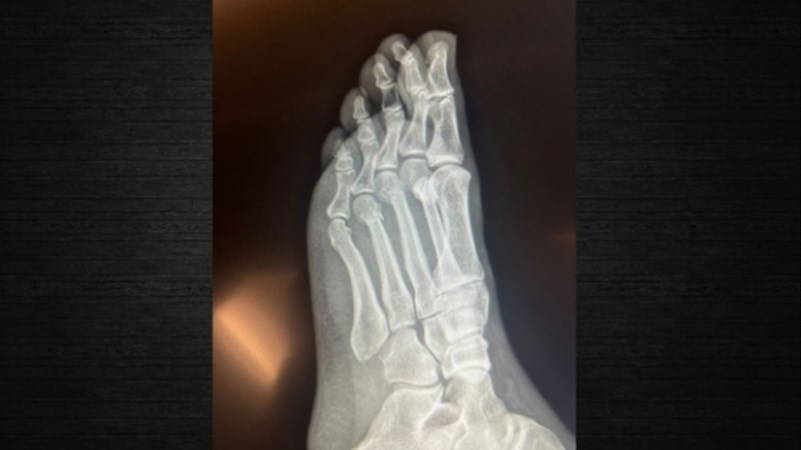

RÖNTGEN FİLMLERİNİ PAYLAŞTI

Röntgen filmlerini paylaşan CHP lideri, iddialara ilişkin olarak “FETÖ’cü hesapların yaydığı bir yalan, daha sonra üzerine eklenerek, boyutlandırılarak kasıtlı olarak devam ettirildi” dedi.

'PARMAK KEMİKLERİ KIRIK'

CHP Genel Başkanı Özgür Özel’in “Herkes inceleyebilir” dediği filmleri inceleyen Ortopedist Prof. Dr. Tarık Yazar da şu değerlendirmeleri yaptı:

“Sayın Özgür Özel’in röntgen filmlerini incelediğimizde parmak kemiklerindeki kırıkları gördüm. Açık bir yara olmaması bir şanstır. Yani, dışarıya kan akmamış. Röntgende yara olup olmadığı her zaman görülmez. Ancak, Özgür Bey’in röntgenini incelediğimizde yine de şanslı olduğunu gördüm. Biz buna ‘şanslı kırık’ deriz. Aslında tam kırık da diyemeyiz. Ayrılmamış, kemiğin özelliği bozulmamış.

İyileşme yeteneğinin fazla olduğu bir bölgede kırık var. Şanslı tarafı kanlanmanın kuvvetli olduğu bir bölgede kırık gördüm. Bilgisayarlı tomografiyle takibi uygun olur. Tedaviye doğru başlanmış. Mutlaka iyileşecektir. Kullandığı ayak desteği gayet doğru bir seçim. Üç aya kalmaz tam iyileşme gerçekleşir. Lütfen bir daha düşmesin."